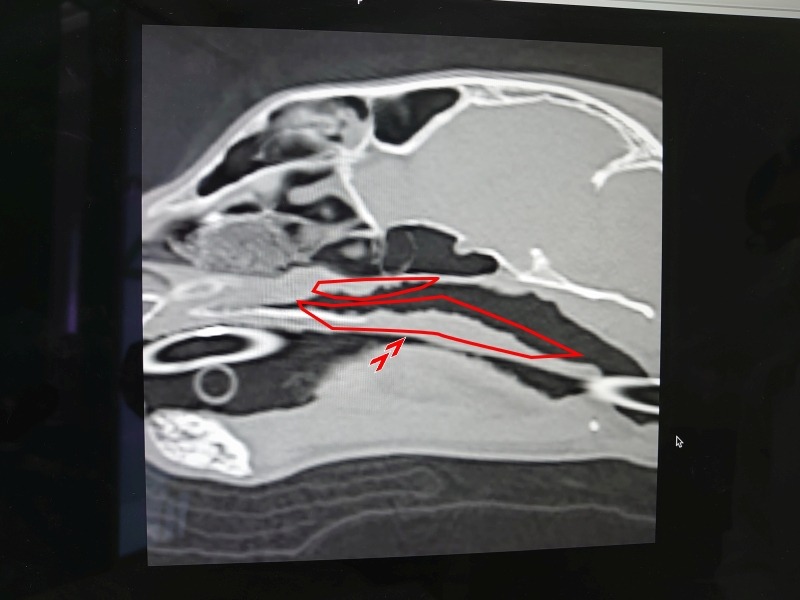

先生からCTと内視鏡の映像を見せてもらった

確かに先日見せてもらったワンちゃんの狭窄とは異なり、空洞は広いようだけど何かがへばりついてる..

先生の所見では今のところこれが炎症によるものなのか、リンパ腫なのかは判断できないとのこと..

鼻咽頭狭窄でバルーンで広げれば..ということで済むと思っていたのにこんな展開..